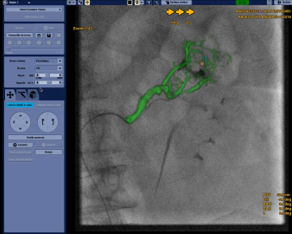

Die automatische Segmentierung von Knochen und Gefäßen und die Mittellinienverfolgung durch den Gefäßverschluss ermöglichen eine schnelle Planung anhand von präoperativen CT- oder MR-Bildern. Durch diese Kombination präoperativer CT- oder MR-Bilder mit Mittellinienverfolgung und Durchleuchtung in Echtzeit können Spezialisten außerordentlich gut sehen, wo die Rekanalisation vorgenommen werden muss und wo sich die Einstichstelle befindet, ohne die Kontrastmittelmenge erhöhen zu müssen.

Vessel ASSIST bietet eine präzise und einfache anatomische Segmentierung und genaue Gefäßquantifizierung anhand von 3D-Volumen. Zudem ermöglichen die erweiterte 3D-Roadmap und erweiterte Bildführungsfunktionen für die frontale und laterale Ebene das sichere Führen von Kathetern.

Vessel ASSIST für Neurointerventionen